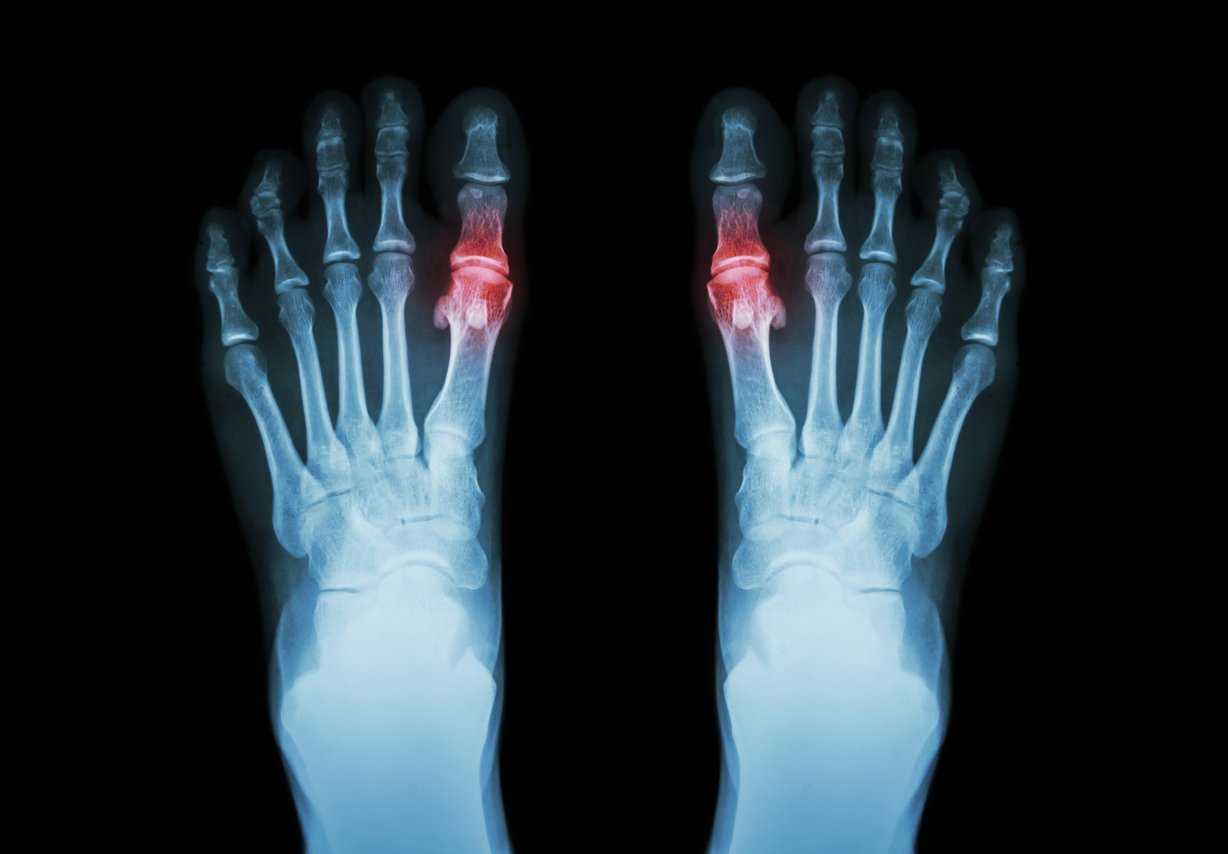

gout , rheumatoid arthritis ( film x-ray both foot and arthritis at first metatarsophalangeal joint ) ( medicine and science background )

Istock

La goutte correspond à une atteinte articulaire inflammatoire, ou arthrite, due à un excès d’acide urique. Elle provoque de violentes douleurs, souvent au niveau du gros orteil. Elle est favorisée par de mauvaises habitudes alimentaires et à tendance à récidiver.